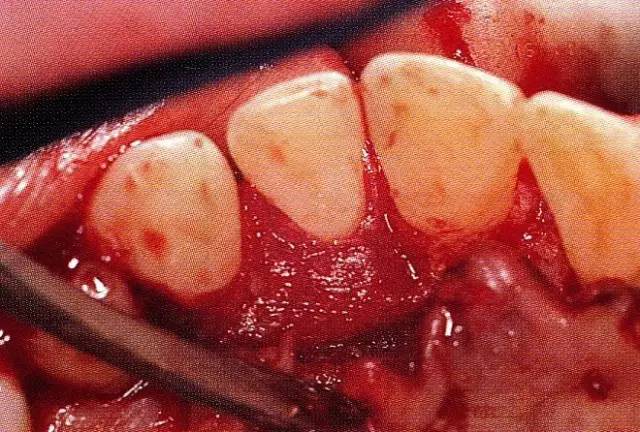

640.webp (9).jpg

▲圖8-3  進(jìn)行全厚瓣翻瓣,將根表面的沉積物、骨缺損的肉芽組織徹底清除,確認(rèn)牙槽骨形態(tài),可看到從頰側(cè)到遠(yuǎn)中存在垂直性和水平性的骨缺損。